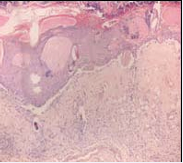

Burn Wound Creation: Using the method described by Sarkhail et al., [11] with some modification, deep partialthickness burn wounds were created on the shaved backs of the rats using a 15-mm diameter temperature-regulated soldering iron (single-channel power unit WD 1000 with 80-watt WSP80; Weller, Besigheim, Germany). The soldering iron was heated to 100° C and placed on the back of a rat for 10 s by free fall, without any pressure from the researcher’s hand. The pressure exerted on the skin corresponded to the 20 g mass of the soldering bar used for the burn induction. To confirm the degree of burn injury, the wound tissues were collected by excision using scalpel blade at 5 min post-burn and used to prepare hematoxylin and eosin (H&E)-stained sections for pathological examination. The H&Estained sections did not show any sign of tissue injury (Figure 1),

Figure 1 Microscopic view of H&E stained at 5 min post-burn. No sign of tissue injury.

indicating that at 5 min post-burn, the cells and tissues had not responded to the injury by homeostasis and inflammation. However, H&E-stained sections obtained on day 7 of injury revealed that deep partial-thickness burns, where a thick crust with epidermal and dermal destruction could be observed (Figure 2).